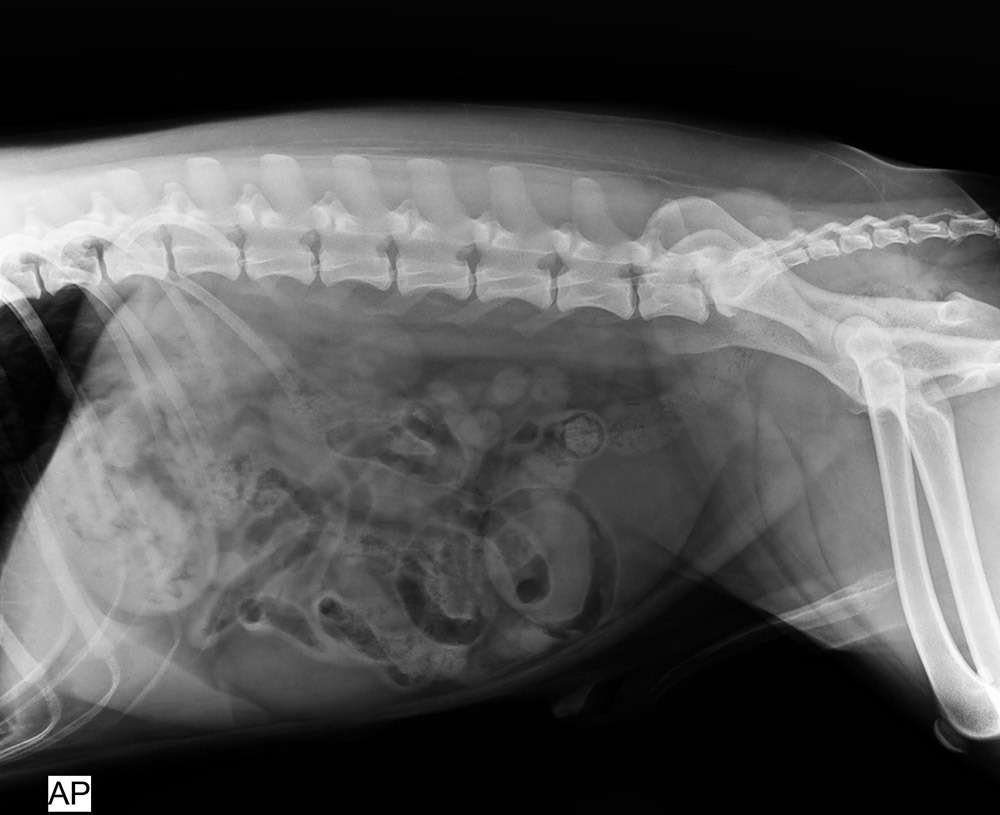

北京愛瑞可動物醫(yī)院

2016/5/31